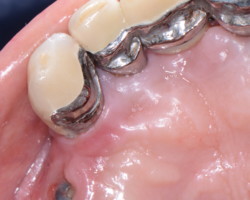

Donner au patient la possibilité d’assurer une hygiène efficace.

Ciment

Il représente un risque X3,6 de péri-implantite (Dalago 2016), un débordement provoquera systématiquement une mucosite et finira en péri-implantite s’il n’est pas éliminé.

Pour Korch et coll (2014), une « mucosite/péri-implantite sur deux est en rapport avec un excès de ciment.

Source : Korch et Coll